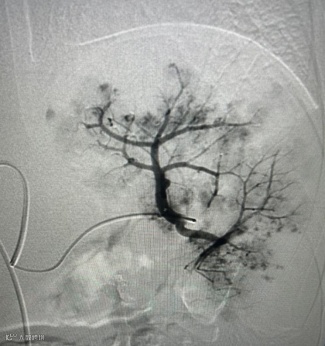

没有大开腹,没有全身麻醉。在患儿勇敢的配合下,手术仅在局部麻醉下进行。医生通过患儿大腿根部一个仅 “针眼”大小的穿刺点,将导管精准送入脾动脉。造影显示,患儿脾脏上下极均有广泛活动性出血,情况危急!

然而,血管外科介入团队沉着冷静,如同精准的导航,通过微导管超选择地将栓塞材料送至出血的血管。瞬间,造影显示活动性出血显著减少,被成功阻断!一场生命的危机,在几乎无创的条件下被化解。

造影脾动脉栓塞以远动脉显影减少,血流速度明显减慢,远端动脉分支造影剂外渗明显减少。